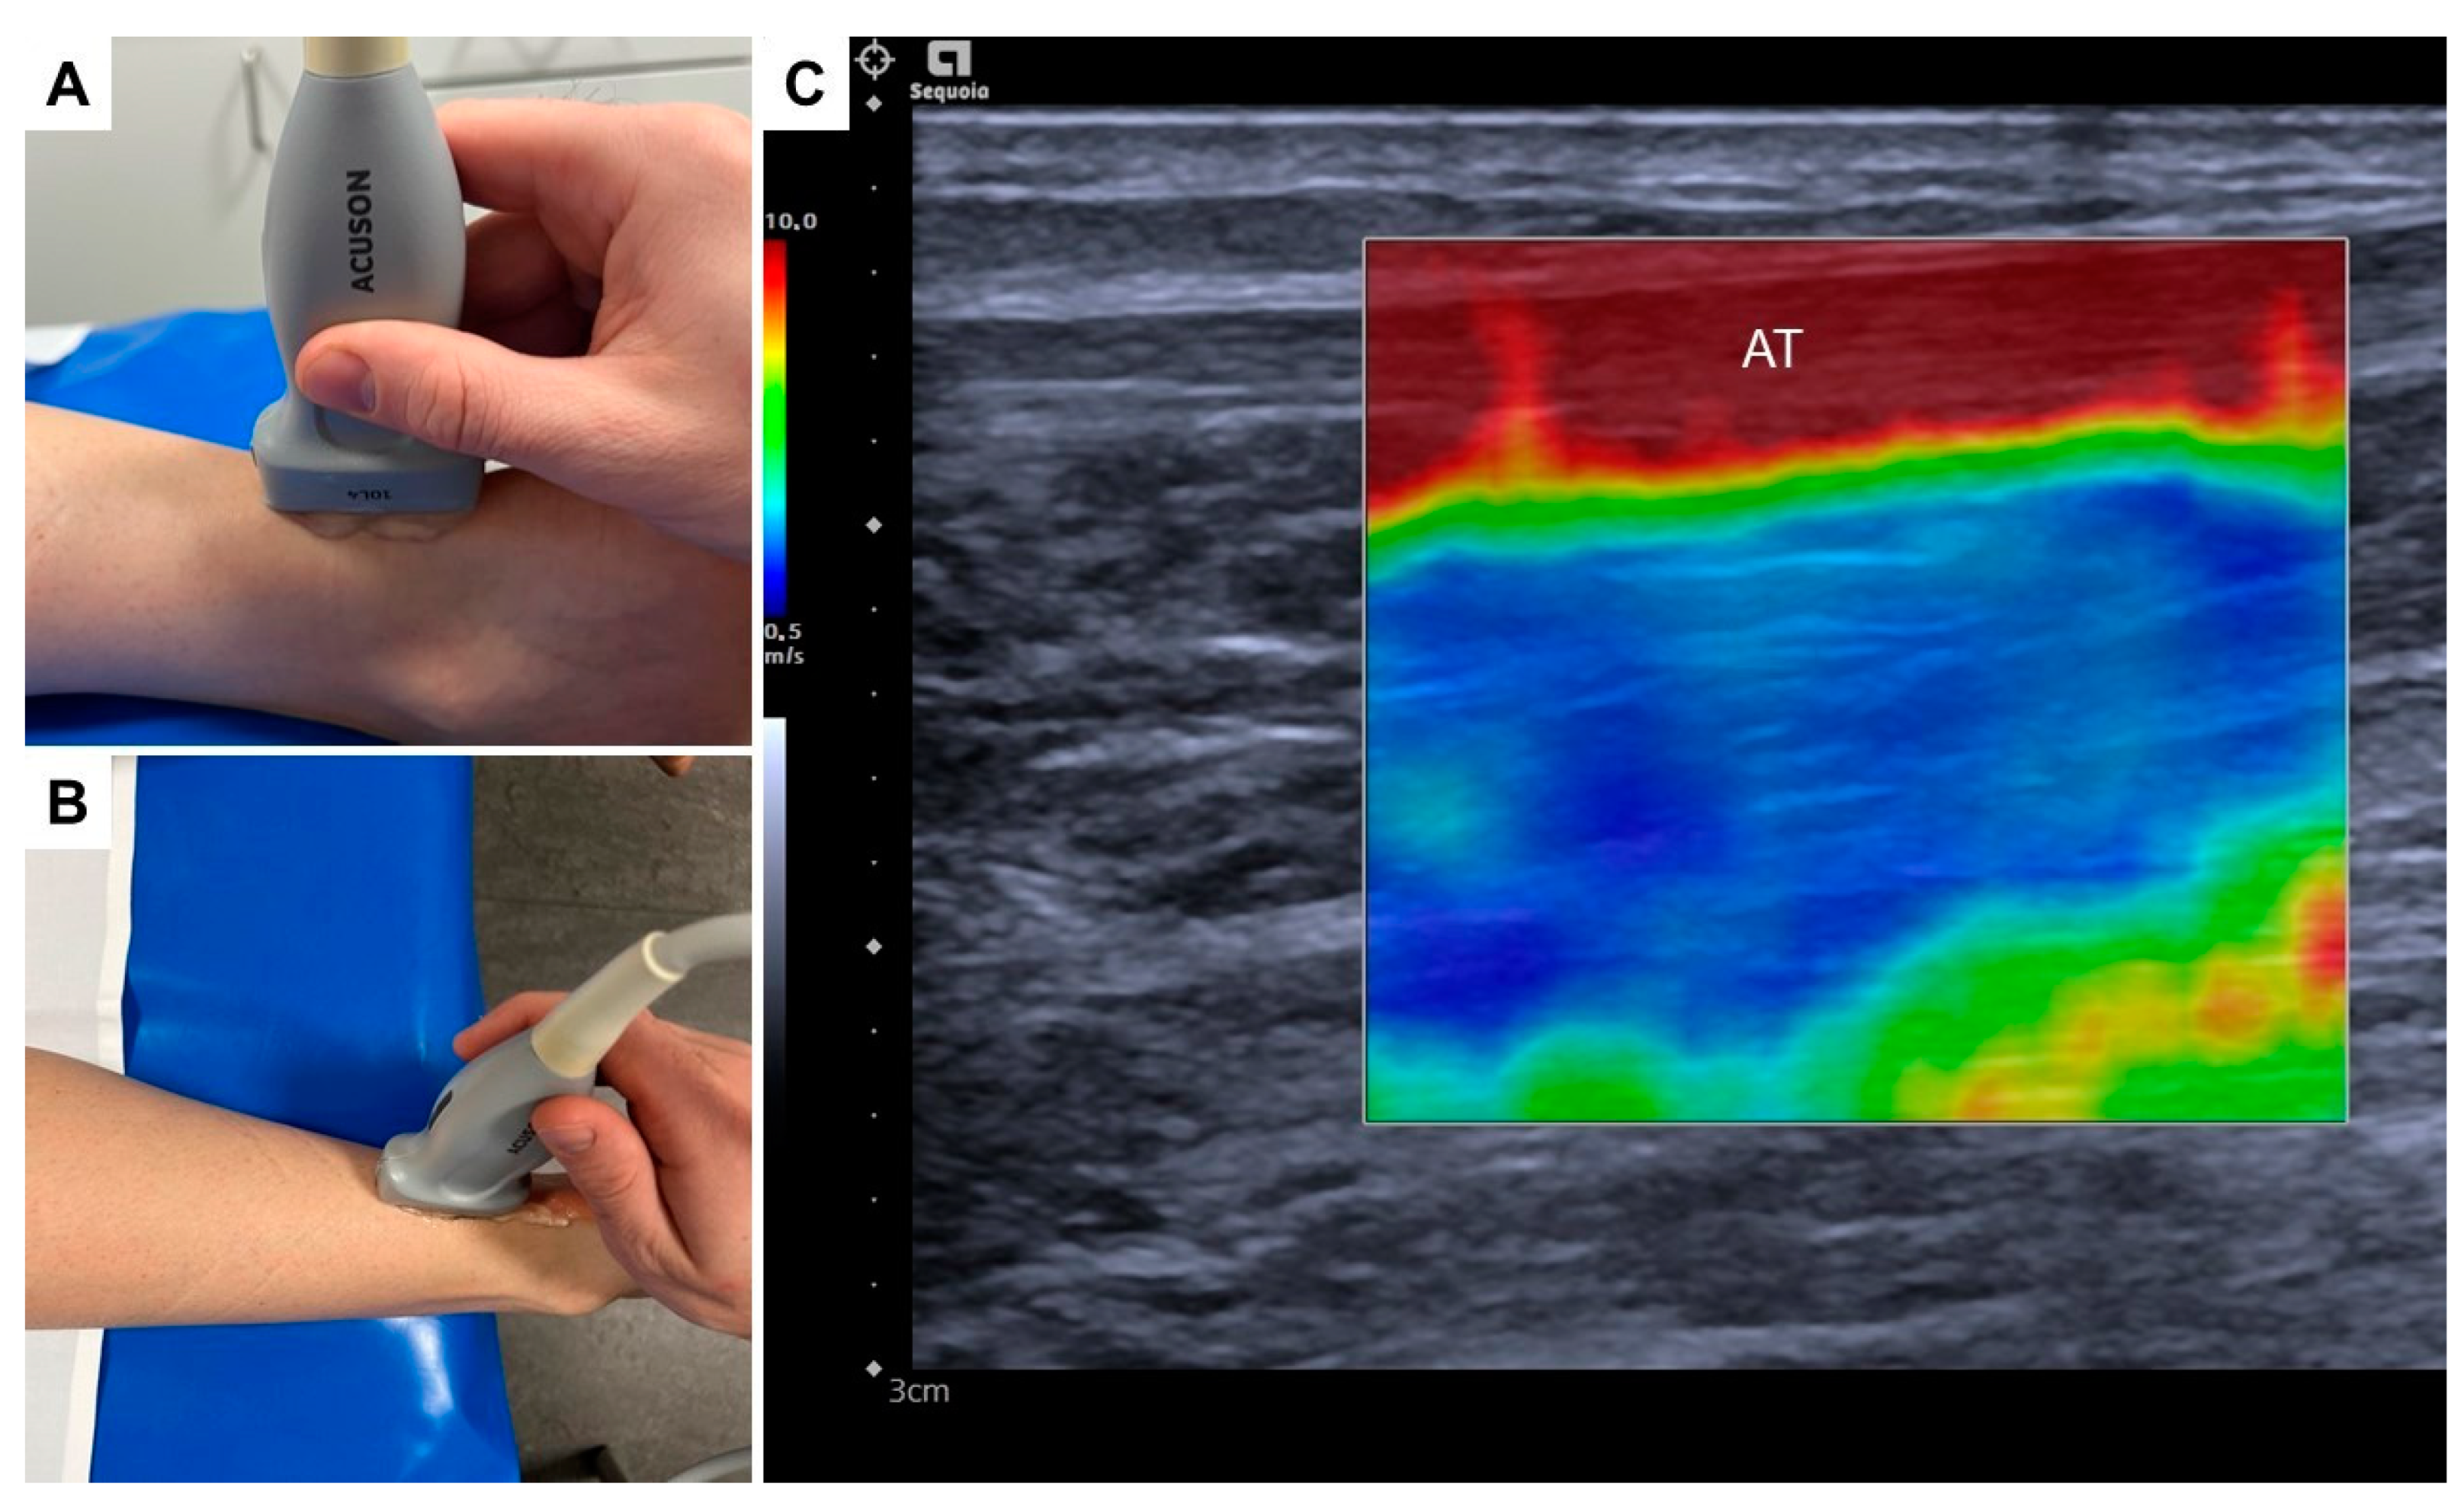

2.2. Shear Wave Elastography Examination